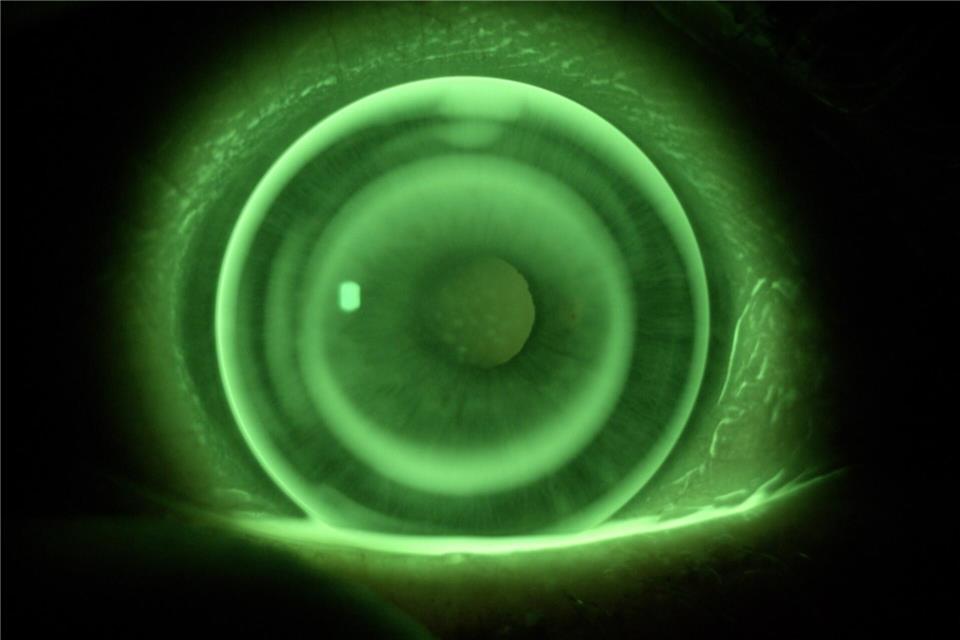

Kontaktlinsen bieten viele Vorteile

Im Magazin „Spezi“ stellt die Borkener Zeitung besondere Unternehmen aus der Region vor - echte Spezialisten auf ihrem Gebiet. Heute: Optik Böckenhoff.